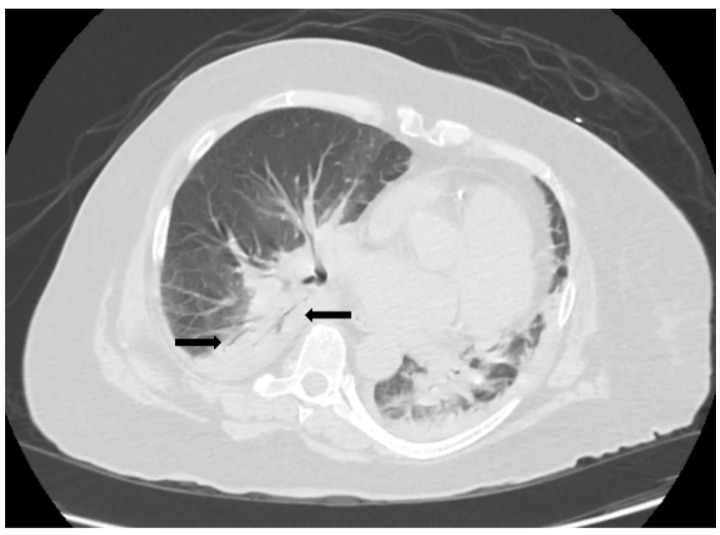

Case presentation: This report describes a rare case of severe anaplasmosis complicated by multiorgan failure in a patient who had undergone splenectomy several decades earlier. The clinical course was notable for pneumonia, acute respiratory distress syndrome, acute kidney injury, rhabdomyolysis, atrial fibrillation, and possible myocarditis. Despite the severity of the presentation, prompt initiation of doxycycline led to recovery, albeit with a significantly prolonged hospital stay.